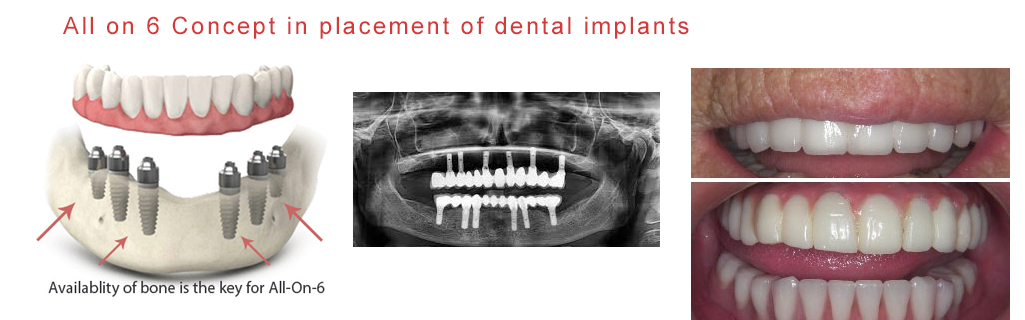

Anybody with an adequate amount of jaw bone in the upper and the lower jaw is a good candidate for this all on 6 dental impant concept. Age is not a barrier. Our oldest patient at Mukha facial surgery & dental implant center for all 6 is a 92 year old lady.